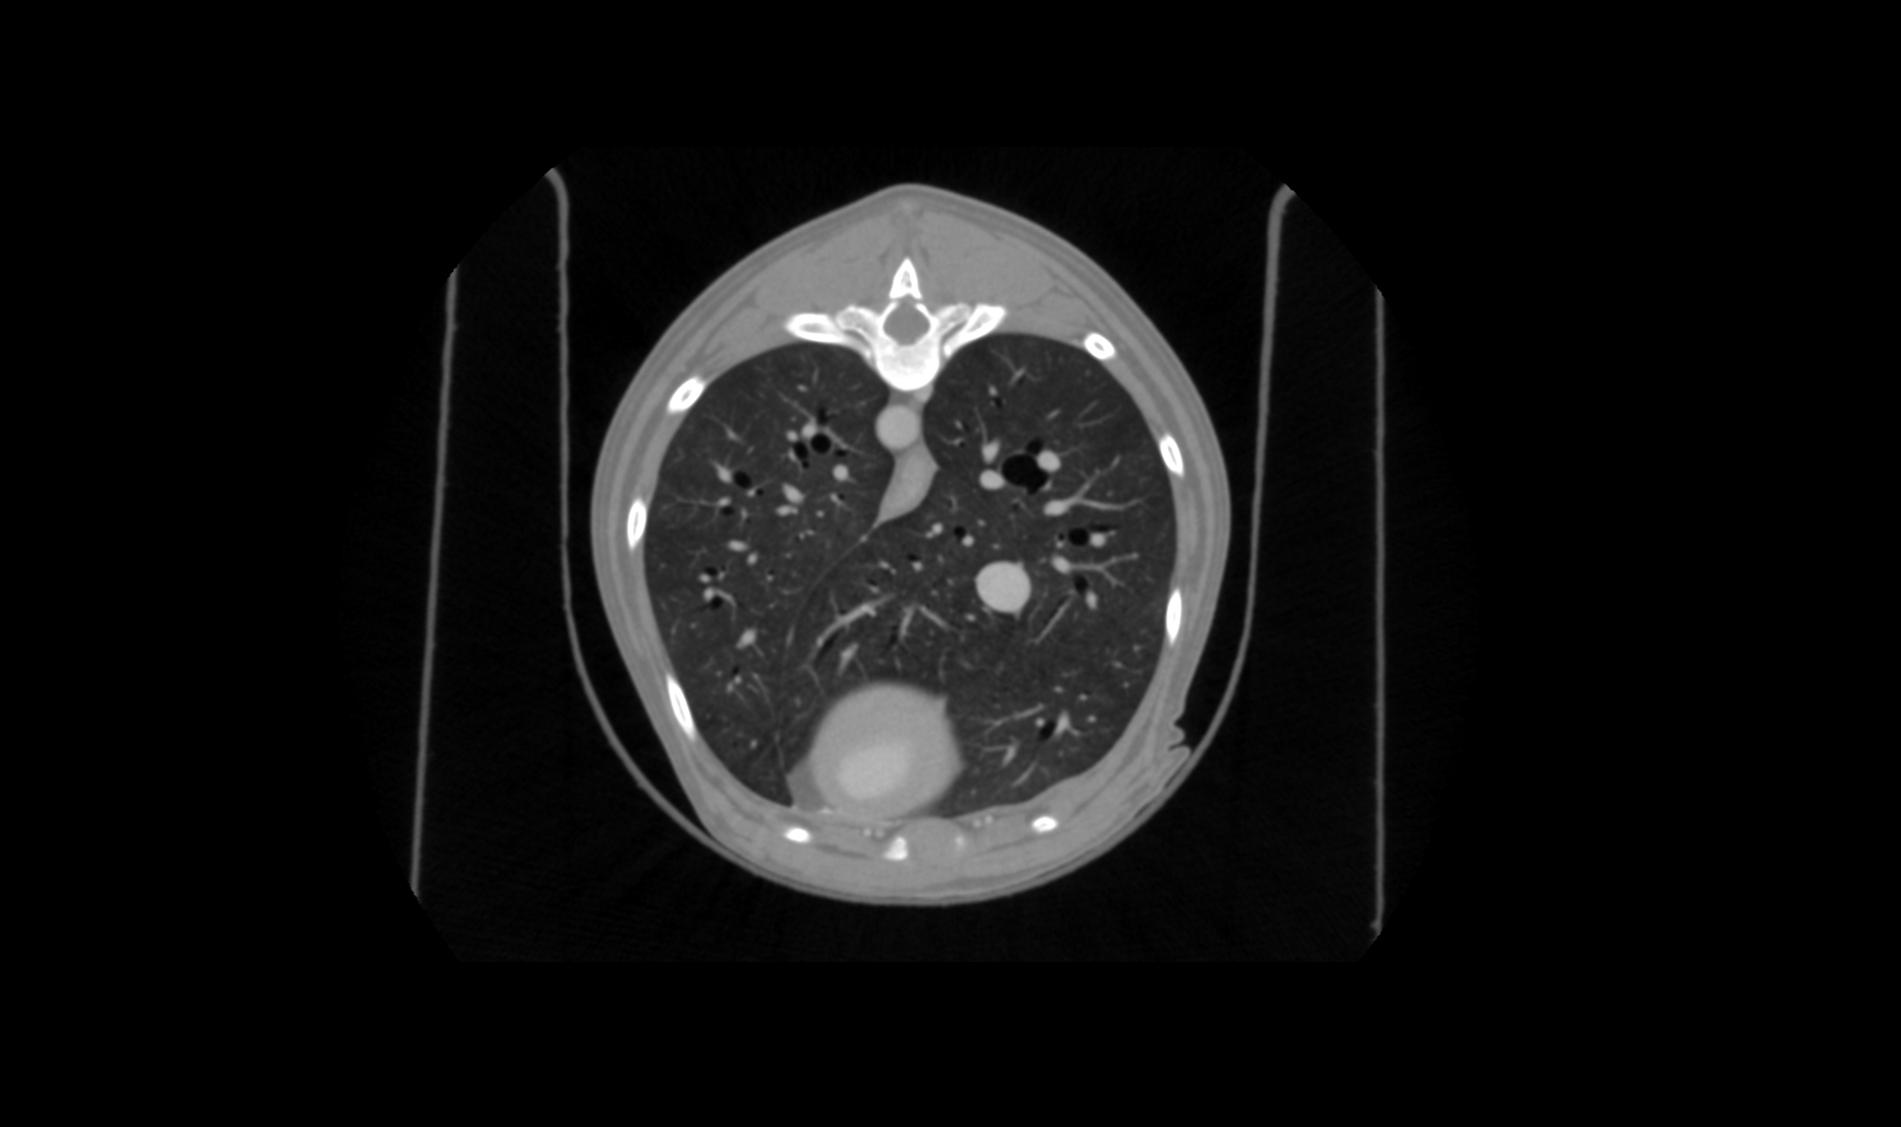

A hybrid operating room integrates imaging systems and surgical tools

A state-of-the-art surgical suite designed to perform complex procedures with maximum precision

Seamless Integration of Imaging and Surgery

Combining CT Scanner, advanced image viewer, and surgical navigation system to ensure precise intraoperative guidance and optimal outcomes.

MULTIMODALITY

Computed Tomography, Fluoroscopy and Digital Radiography all in one.

DIAGNOSTIC AND INTRAOPERATIVE

Diagnostic, preoperative, intraoperative and postoperative environments.